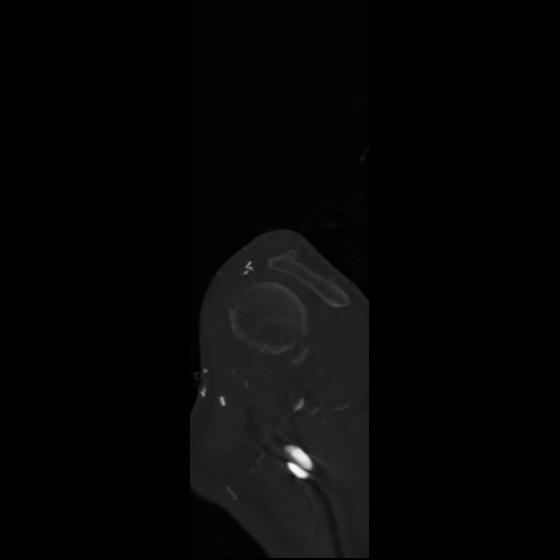

24 ANGIO,CE,Sag-MIP,5.000,ANGIO,Sag-MIP,